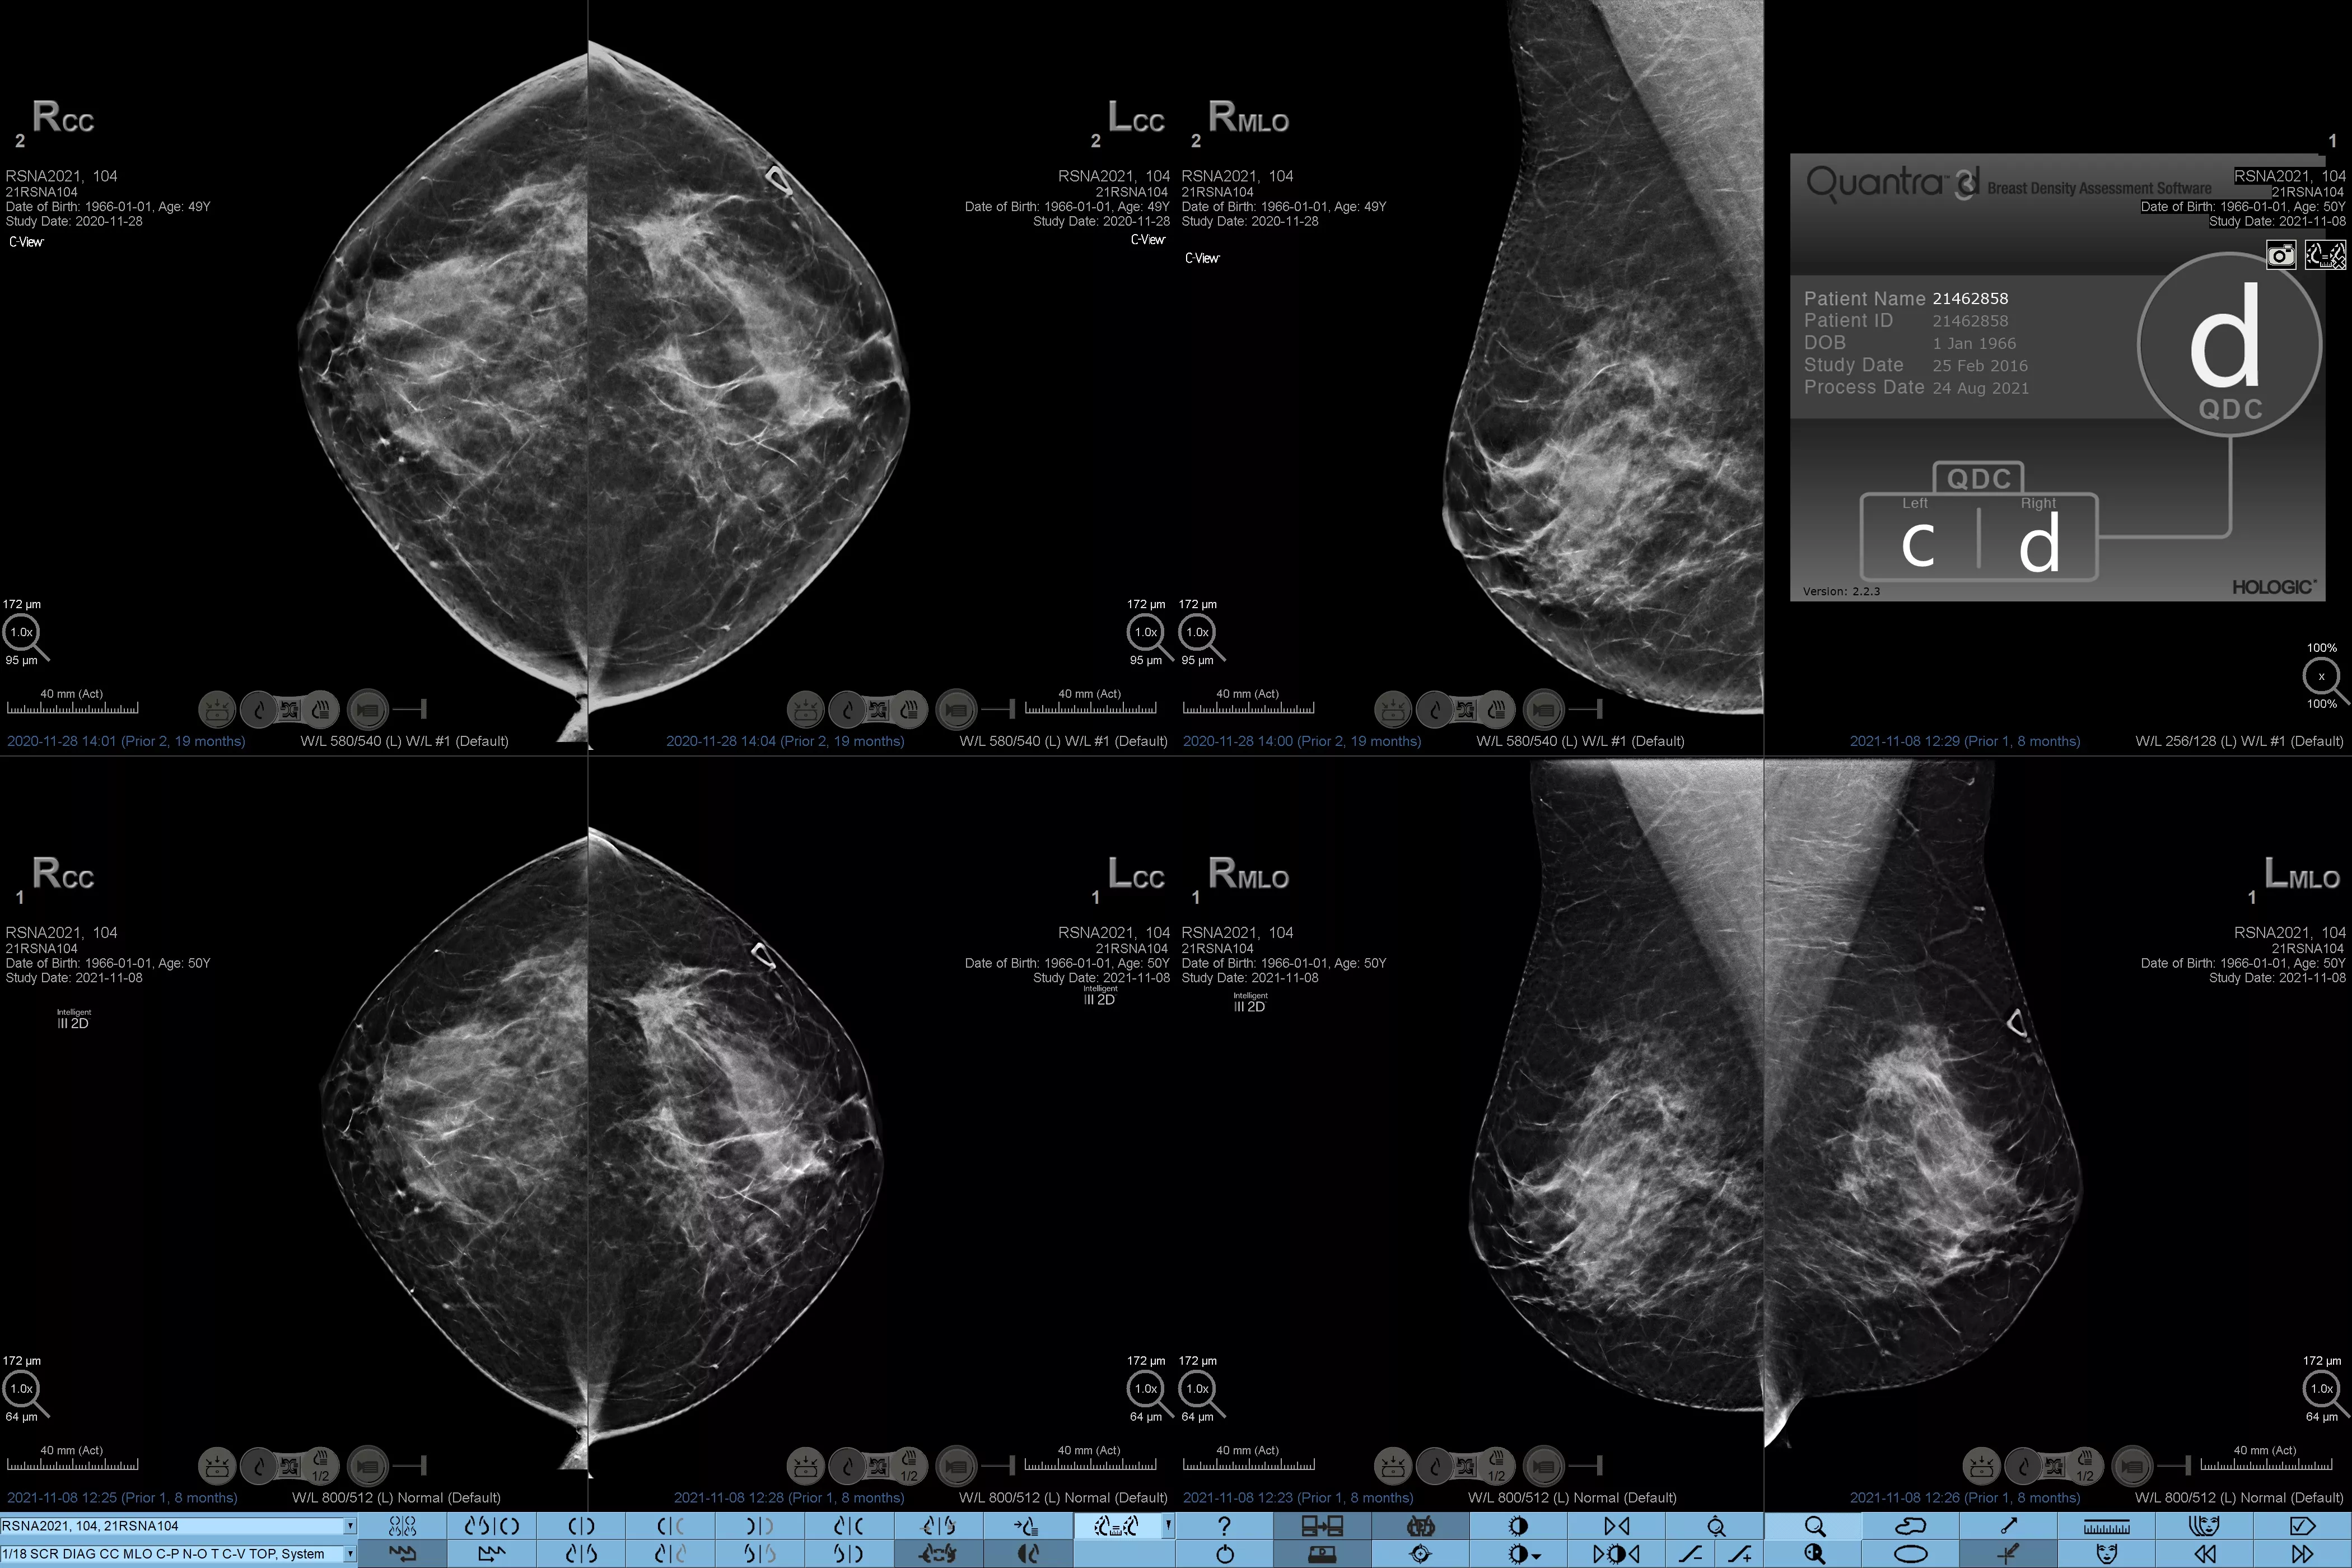

On sait qu’une densité mammaire plus élevée augmente le risque de cancer du sein chez la femme.1 Une analyse précise et objective s’avère donc primordiale. Optimisé par l’apprentissage automatique, le logiciel de la technologie Quantra analyse les images 2D™ et de tomosynthèse pour déterminer la distribution et la texture du tissu parenchymateux. Il classe les seins selon quatre catégories de composition, conformément aux recommandations de l’American College of Radiology (ACR) BI-RADS Atlas 5th Edition.2

Images de mammographies